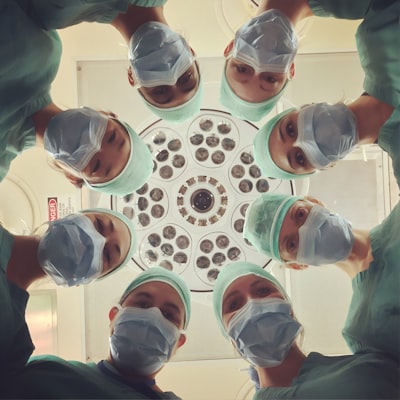

Doctors often use local anesthetics for many medical procedures. These include minor surgeries, dental work, and nerve blocks. They offer good pain control during and after these procedures, making patients feel more comfortable and reducing discomfort. Depending on the situation, local anesthetics can be given as a cream, through injection, or by infusion.